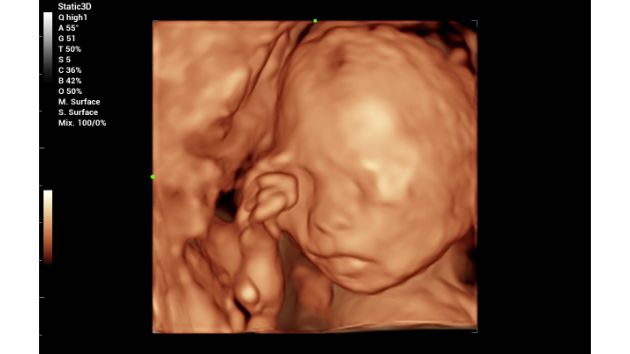

Fetal Embryo 4D

Fetal Face iLive+